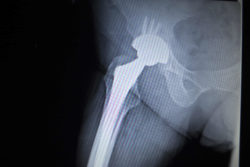

When a hip implant fails, patients undergo hip revision surgery to remove and replace the device in order to prevent potentially irreversible complications. Unfortunately, metal hip revision surgery has a lower success rate than the initial implantation.

Revision surgery entails not only the removal of the problematic prosthesis, but also the cement, surrounding tissue, and dead bone. Then, a new prosthesis is inserted.

The risks associated with hip revision surgery are similar to the original surgery’s risks. However, hip revision surgery has a lower success rate than the initial implantation. This is because the bone is weaker.